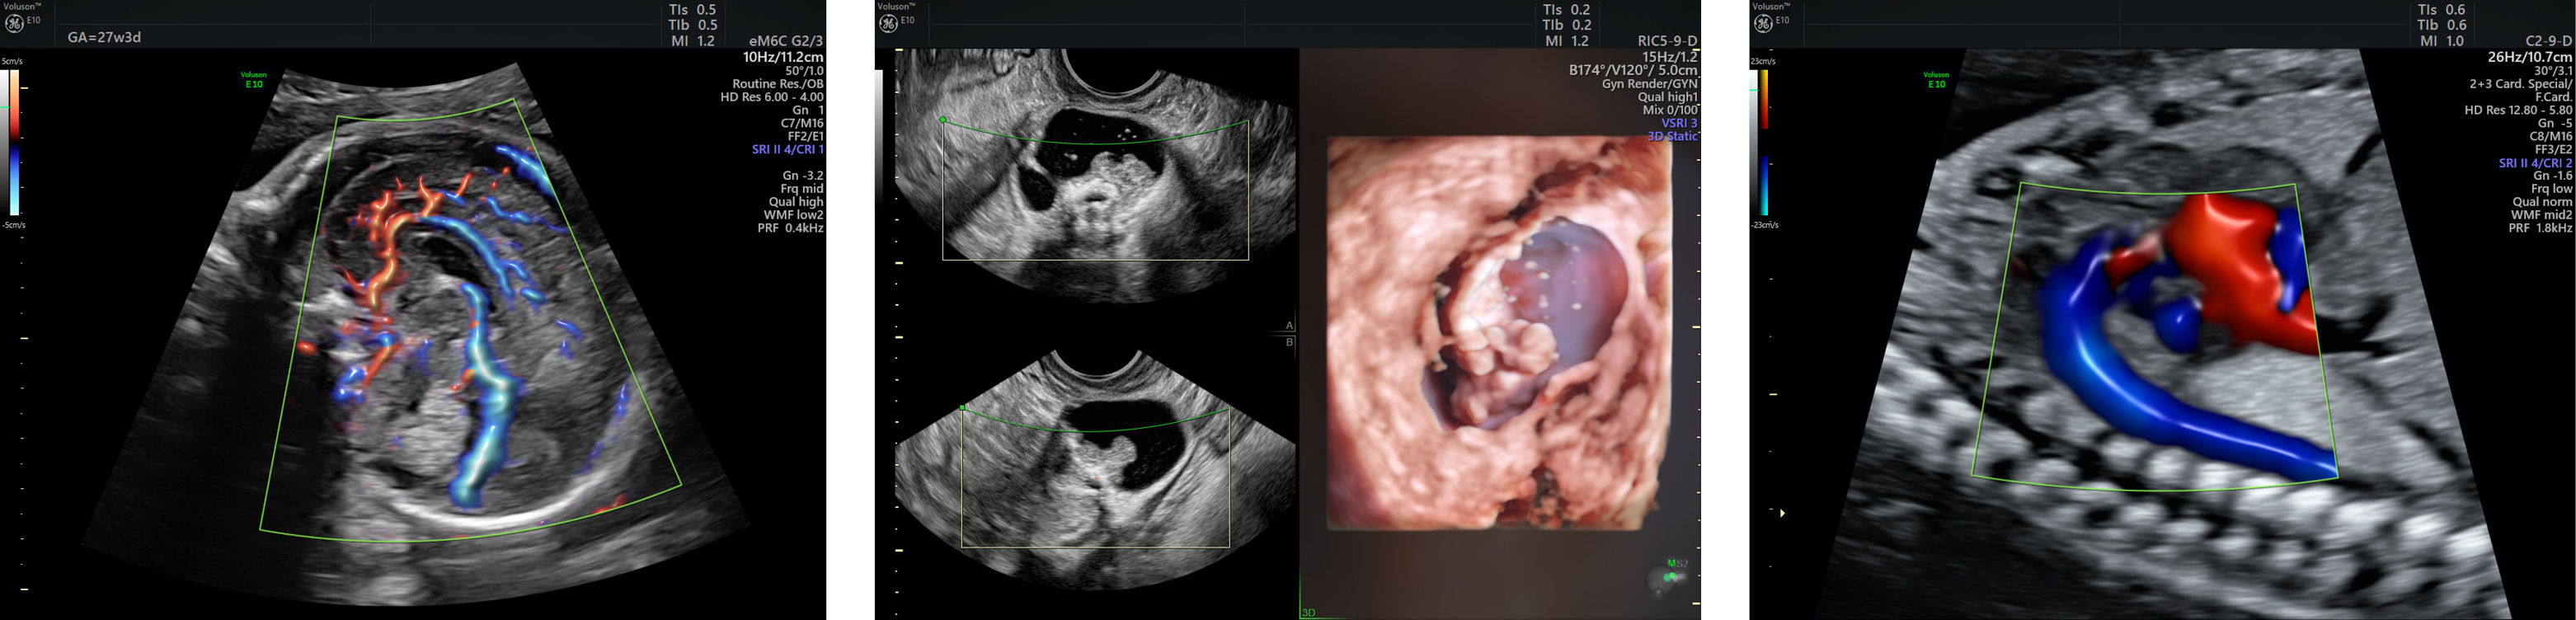

3d ultrasound in los angeles california. 4547 w rosecrans ave. The ge voluson 730 4d ultrasound technology provides a three dimensional real time live action view of your baby. Beginning with gender determination as early as 18. Our 3d 4d packages are affordable to every expectant mom and dad and provide you with timeless videos and photos as keepsakes of your baby for your family to enjoy for years to come.

East los angeles 3d 4d ultrasound. Sol had said ill make you a deal baby more. Latest technology 3d 4d ultrasound los angeles optima diagnostic imaging takes pride in providing the latest diagnostic equipment in partnership with top medical technicians fully trained and up to date on the latest improvements in the equipment. It features advanced signal processing which produces higher quality ultrasound images and is the ultrasound machine used in every first look sonogram facility.

Call today for an appointment. Ultrasound baby images is 3d 4d ultrasound imaging center for unborn babies conveniently located in valley village ca adjacent to studio city north hollywood and sherman oaks of los angeles ca. At prenatal imaging centers our experts in 3d ultrasound and 4d ultrasound will help you capture those precious first moments of your babys life. 3d 4d ultrasound is similar to your doctors meaning that it is not harmful or invasive to you or your babybut with our 3d 4d option you will be able to see what your baby looks like.